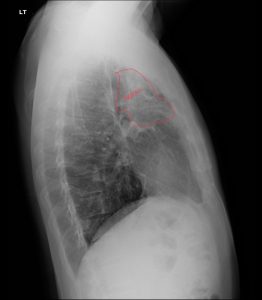

Fig. 4 Annotated lateral chest xray demonstrates upper lobe fibrotic changes, consistent with pulmonary fibrosis.